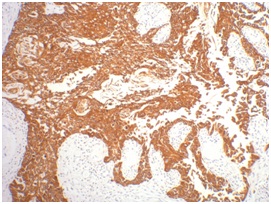

Keratin 16 is expressed in keratinocytes, which are undergoing rapid turnover in the suprabasal region (also known as hyperproliferation-related keratins). Keratin 16 is absent in normal breast tissue and in noninvasive breast carcinomas. Only 10% of the invasive breast carcinomas show diffuse or focal positivity. Reportedly, a relatively high concordance was found between the carcinomas immunostaining with the basal cell and the hyperproliferation-related keratins, but not between these markers and the proliferation marker Ki-67. This supports the conclusion that basal cells in breast cancer may show extensive proliferation, and that absence of Ki-67 staining does not mean that (tumor) cells are not proliferating.

IHC staining of human gullet cancer tissue with CK16 mouse mAb(7F7) diluted at 1:200.